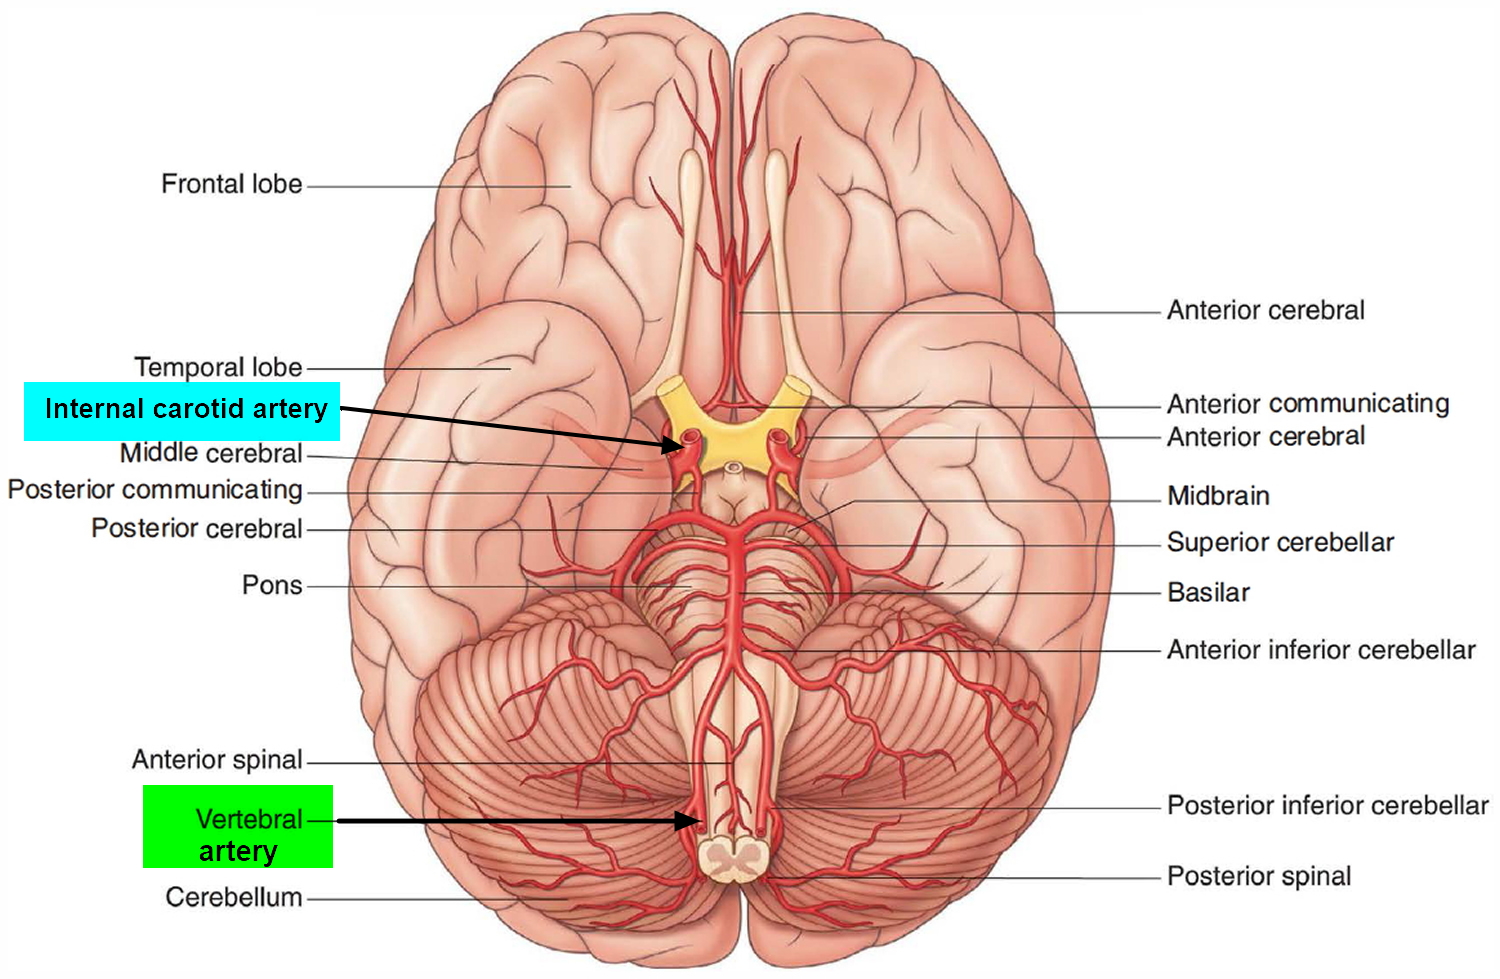

Анатомия: Задняя соединительная артерия мозга

Раздел: Фотоэссе